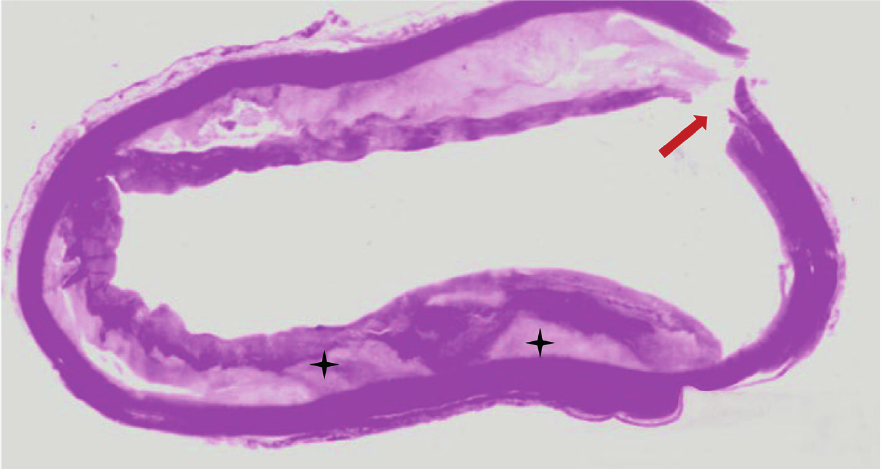

Figure 2

Microscopic view of atheromatous ascending aorta. The patient underwent emergency Bentall de Bono surgery for acute aortic dissection Stanford A; however, she died during the intervention. Circumferential atheromatous plaque in ascending aorta with cholesterol deposits in the subintimal layer (black asterisks). The aortic dissection entry flap can be seen (reddish arrow).